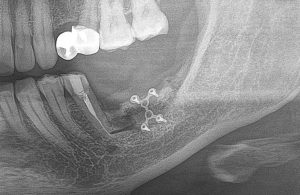

После операции мы делаем контрольные снимки. Это может быть ортопантомография:

или конусно-лучевая компьютерная томография. Как вам больше нравится.

Результат остеопластики методом остетотомии мы можем оценить уже через 4 месяца. Перед этим сделаем контрольные снимки (слева «до», справа «через 4 мес»):